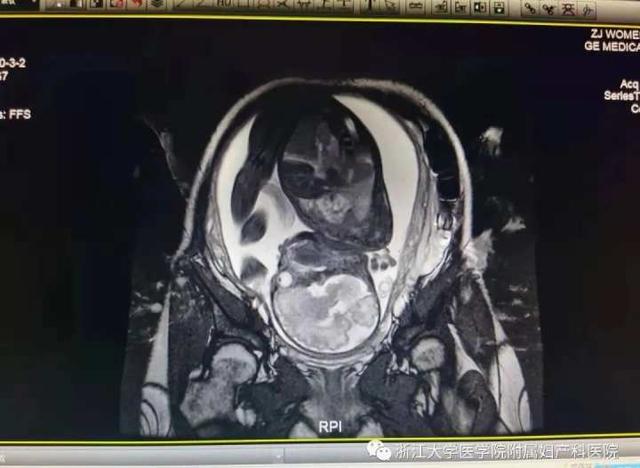

“我们上一次发表,应该是怀孕30周左右。之后我们还是每周检查疤痕,发现疤痕厚度稳定在1.0 mm左右,没有再出现之前的向外鼓包。b超监测宝宝的生长发育,结果也不错。在第32周,我们进行了另一次磁共振成像(MRI)来检查子宫疤痕的愈合情况。虽然提示段依然较薄,但无羊膜囊肿胀,明显好于以前。”团队成员严丰一直在密切关注安静的情况,并努力延长胎龄。

术中发现修复后的子宫肌层完整性非常好。